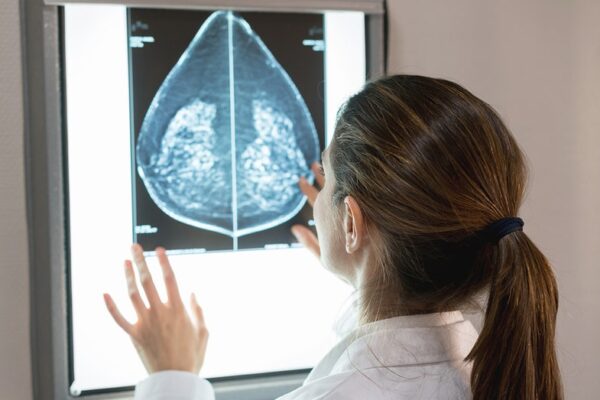

FDA approves first AI tool to predict breast cancer risk

The U.S. Food and Drug Administration (FDA) has approved the first artificial intelligence (AI) tool to predict breast cancer risk. The authorization was confirmed by digital health tech company Clairity, the developer of Clairity Breast – a novel, image-based prognostic platform designed to predict five-year breast cancer risk from a routine screening mammogram. In a…